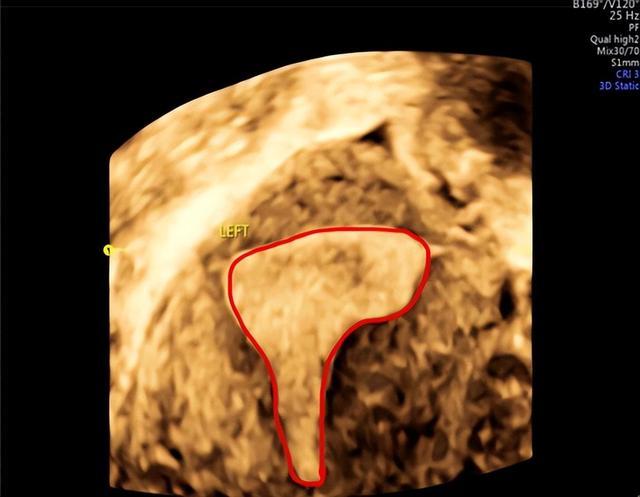

下图是正常宫腔,呈倒置三角形态。

而在下面这张图我们可以看到:宫腔失去了正常倒三角的形态,下段宫腔因为粘连导致缩窄呈窄桶状。